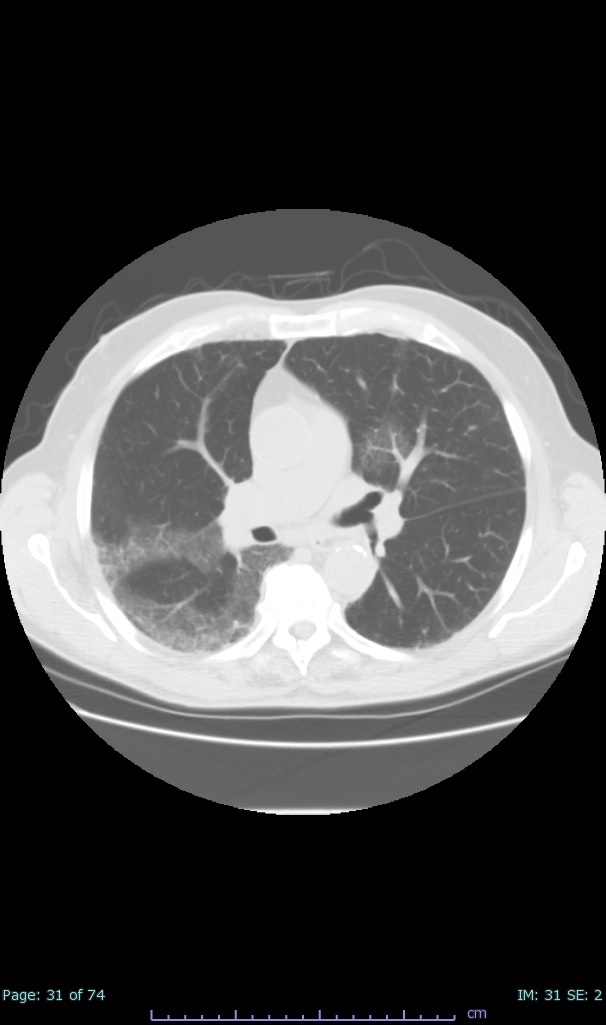

- 100% subpleural involvement, 33% + centrolobular involvement

- 40% even apical/basilar, 27% basilar dom, 5% mid dom. 1/17